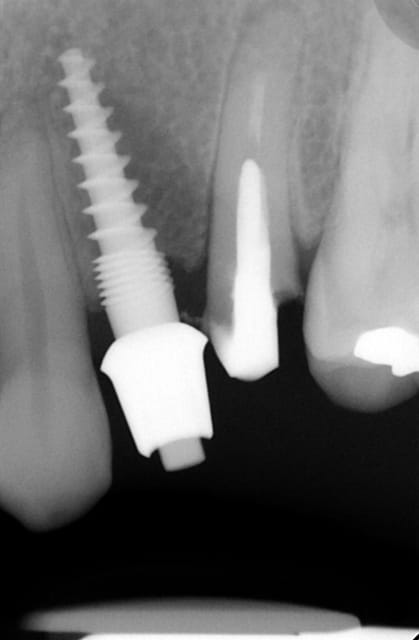

Oui ca semble ....sur la opg radio tu peux voir la situation seulement deux semaines après l´implantation immédiate 34 jusqu´à 36 et 45, les derniers 2 photos montrent la même situation après un an ( où on a enlevé la supra construction pour un contrôle). Sur ce cas je voulais montrer la bonne régénération osseuse et de la gencive.

Oui,c´est un Prep cap zircone , que je cémente juste après l´implantation immédiate pour mieux former la gencive. Les implants monoblocs ont étés implantés entre 40 et 60 Ncm . Les photos 6 et 8 on voit les prep cap juste après l´implantation immédiate ce sont des sortes de "couronnes" pré fabriquées.